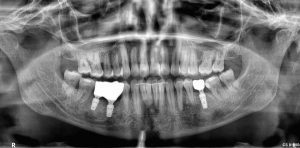

Dr. Toni Flichy

Implantes Inmediatos en Sector Anterior con Carga Inmediata

Implante con carga inmediata BOPT y regeneración simultánea flapless de tejidos blandos y duros